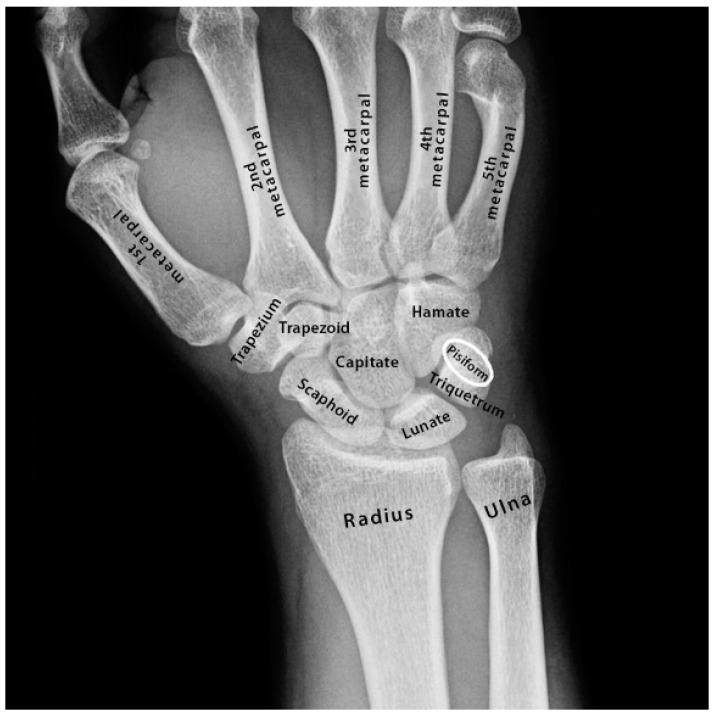

The human capacity to speak is fundamental to our advanced intellectual, technological and social development. Yet so very little is known regarding the evolutionary genetics of speech or its relationship with the broader aspects of evolutionary development in primates. In this study, we describe a large family with evolutionary retrograde development of the larynx and wrist. The family presented with severe speech impairment and incremental retrograde elongations of the pisiform in the wrist that limited wrist rotation from 180° to 90° as in primitive primates. To our surprise, we found that a previously unknown primate-specific gene had been disrupted in the family. emerged de novo in an ancestor of extant primates across a 540 kb region of the genome with a pre-existing highly conserved long-range laryngeal enhancer for a neighbouring bone morphogenetic protein gene . We used transgenic mouse modelling to identify two additional long-range enhancers within that regulate expression in the wrist. Disruption of in the affected family blocked the transcription of across the 3 enhancers in association with a reduction in expression and retrograde development of the larynx and wrist. Furthermore, we describe how developed a human-specific promoter through the expansion of a penta-nucleotide direct repeat that first emerged de novo in the promoter of in gibbon. This repeat subsequently expanded incrementally in higher hominids to form an overlapping series of Sp1/KLF transcription factor consensus binding sites in human that correlated with incremental increases in the promoter strength of with human having the strongest promoter. Our research indicates a dual evolutionary role for the incremental increases in transcriptional interference of enhancers in the incremental evolutionary development of the wrist and larynx in hominids and the human capacity to speak and their retrogression with the reduction of transcription in the affected family.